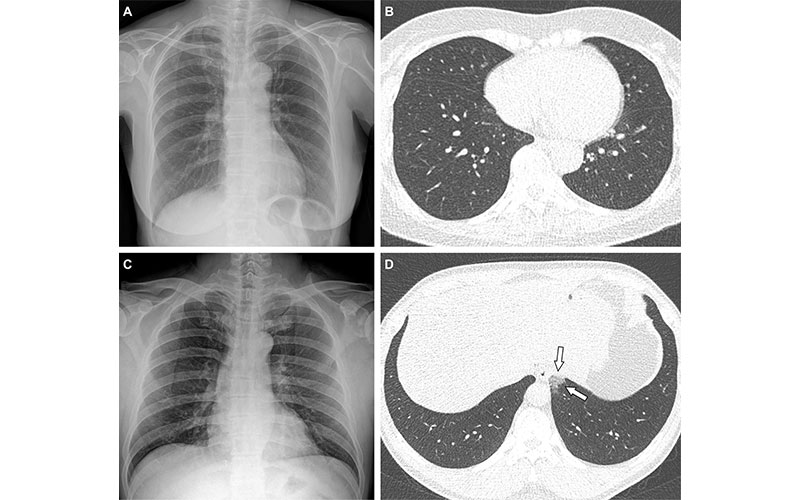

Representative cases showing pneumonia extents and patterns on chest X-ray (CXR) and CT images. (A and B) A 65-year-old female with breakthrough infection 2 months after a second dose of the Pfizer vaccine (fully vaccinated). The patient had a history of hypertension. (A) CXR obtained at admission showing no abnormal opacification in both lung zones. The CXR extent of pneumonia was scored as 0 (no evidence of pneumonia). (B) Axial chest CT image at the lower lobe level (obtained on the same day) showing negatively for pneumonia; CT extent of pneumonia was scored as 0 (no evidence of pneumonia). (C and D) A 48-year-old male with 1 month after a first dose of the AstraZeneca vaccine (partially vaccinated). The patient had no history of comorbidity. (C) CXR obtained at admission showing no abnormal opacification in both lung zones. The CXR extent of pneumonia was scored as 0 (no evidence of pneumonia). (D) Axial chest CT image obtained on the same day showing unilateral ground-glass opacity with a non-rounded morphology in the left lower lobe (arrows). CT extent of pneumonia was scored as 1 (1-25% involvement) and this case was classified as indeterminate appearance of COVID-19 according to the RSNA chest CT classification system.